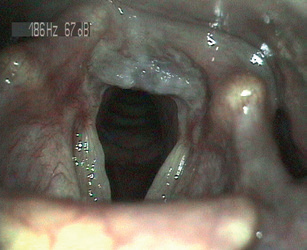

Laryngoskopické vyšetření hrtanu

V otorinolaryngologii máme výhodu možnosti laryngoskopického vyšetření hrtanu. Vchod do hrtanu a vchod do jícnu jsou anatomicky velmi blízko, proto můžeme na sliznici hrtanu u nemocných s EERCH pozorovat četné slizniční změny (obr. 2). Slizniční změny hrtanu, které jsou charakteristické pro mimojícnové projevy refluxní choroby jícnu, byly popsány (Belafsky 2001) a jsou dobrým vodítkem k diagnostice EERCH. K usnadnění hodnocení slizničních změn na sliznici hrtanu je možné použít nástroj Reflux Finding Score (RFS) (tab. 5).